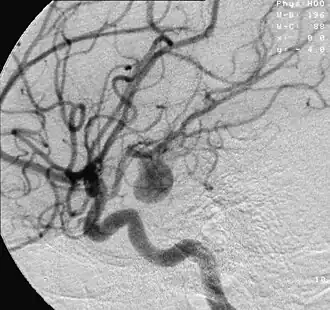

Anévrismes intracrâniens

Leur rupture provoque un accident vasculaire cérébral souvent grave.